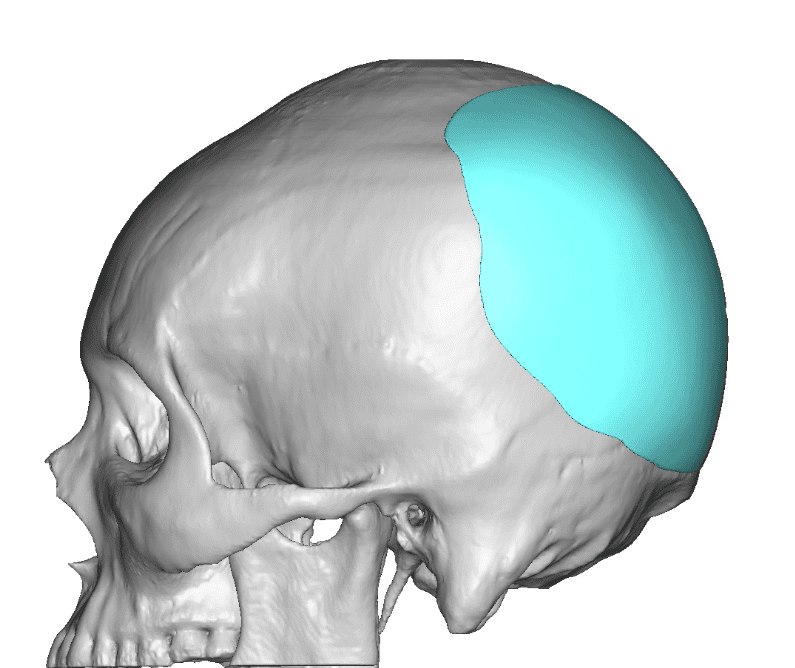

Patient 51

Desire for taller and rounder head shape.

Two stage custom skull implant augmentation technique.

Desire for taller and rounder head shape.

Two stage custom skull implant augmentation technique.